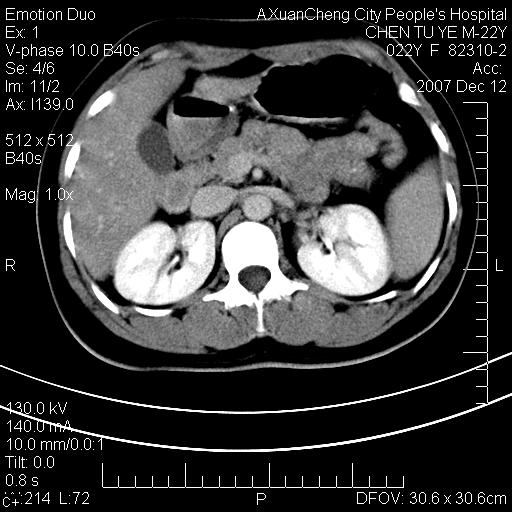

超声提示肝右前叶占位,约2.5cm.

各位战友看看病灶在什么地方,可是右前叶进肝裂部低密度影,平扫ct值约10以下,增强后增高明显

平扫与增强ct值差>10hu的话,应该列为高度疑似病例,我们的职责就是不能放过这样小的病灶.再次b超对比

确定是否同一病灶!运到伪影我坚决反对!

不均匀脂肪浸润,版主所说的病灶为肝园韧带服着点。

考虑肝圆韧带。